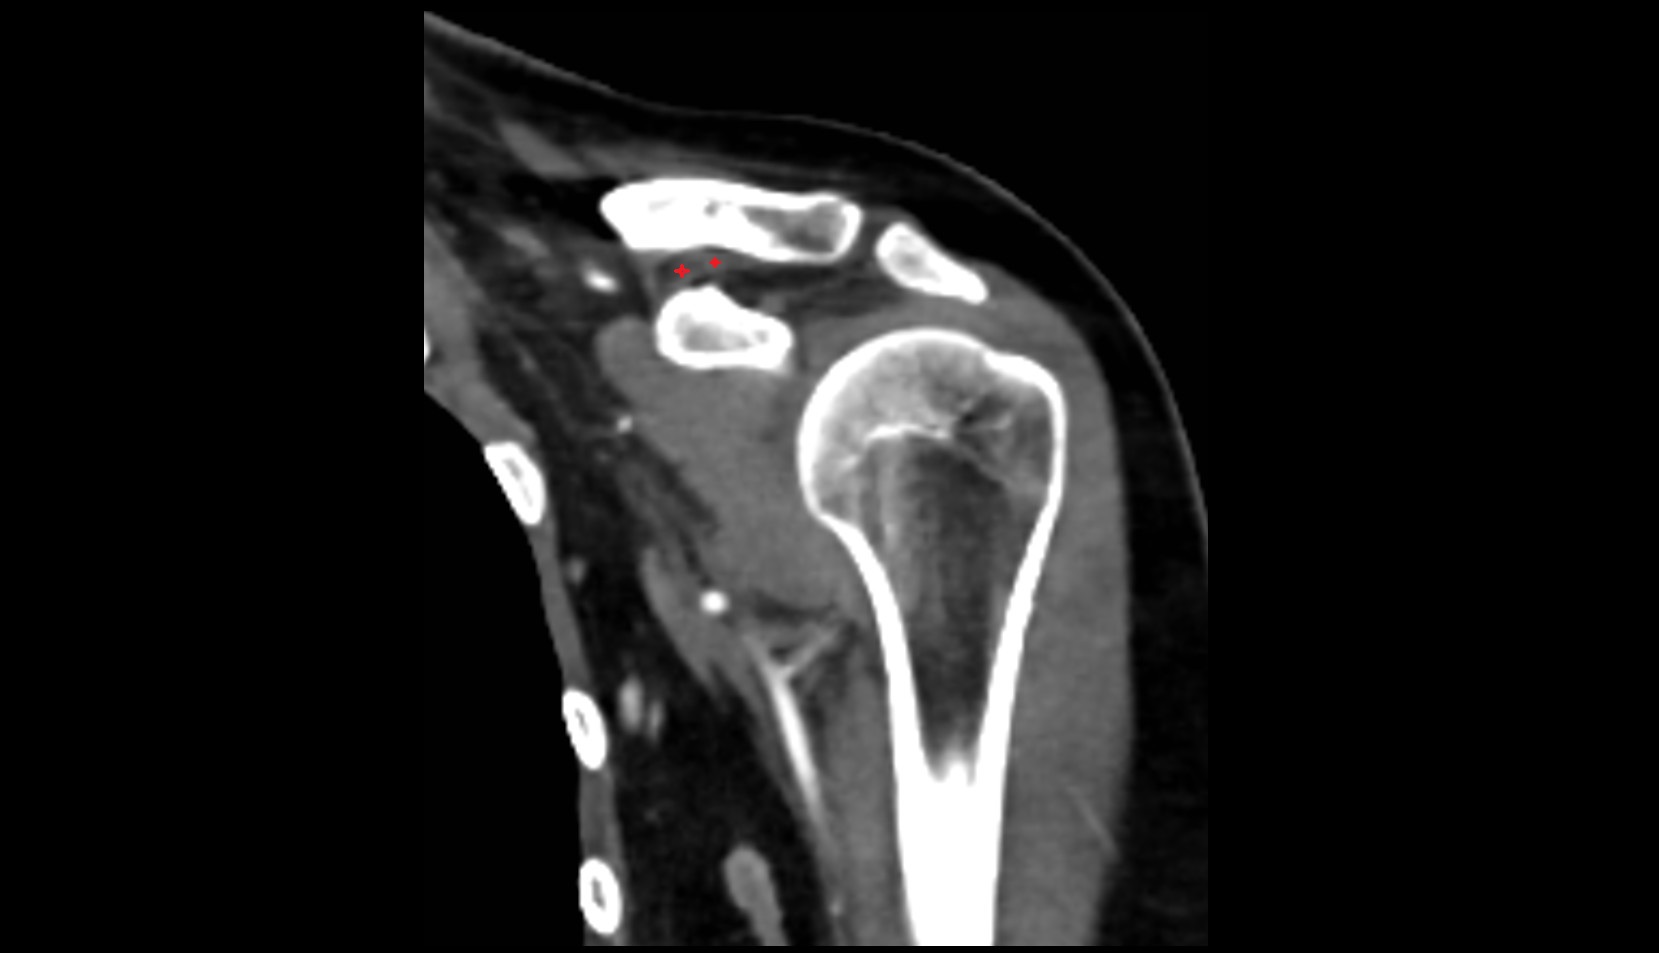

- Shoulder joint (glenohumeral joint)

- Acromioclavicular joint

- Subacromial space